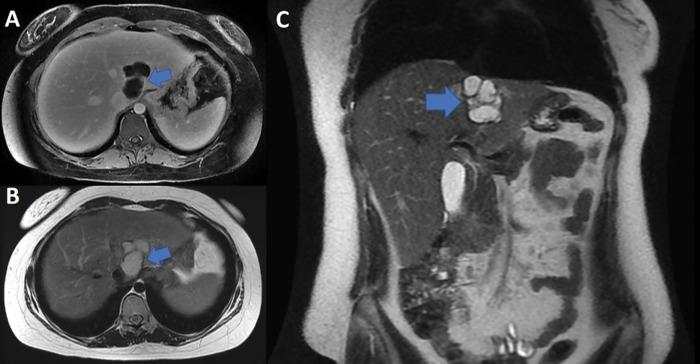

胆管黏液性囊腺瘤:文献综述

Biliary Mucinous Cystadenoma: A Review of the Literature.

Biliary mucinous cystadenomas are cystic neoplasms commonly mistaken for simple cysts. They are rare and generally benign tumors, often incidentally found on imaging and during unrelated surgical interventions. They tend to be slow growing though may reach symptomatic dimensions. Misdiagnosis of biliary mucinous cystadenomas may have serious consequences secondary to their potential for malignant transformation into biliary mucinous cystadenocarcinomas. Here, we review the epidemiology, etiology, pathology, diagnostic modalities, histology, and available treatment methods for mucinous cystadenomas reported in current literature.

摘要

胆管黏液性囊腺瘤是一种囊性肿瘤,常被误诊为单纯囊肿。它们是罕见的肿瘤,通常为良性,常在影像学检查或无关手术中偶然发现。虽然生长缓慢,但可能会发展到出现症状的大小。胆管黏液性囊腺瘤的误诊可能会导致严重后果,因为它们有可能恶变为胆管黏液性囊腺癌。在此,我们综述了当前文献中报道的黏液性囊腺瘤的流行病学、病因、病理、诊断方法、组织学及可用的治疗方法。